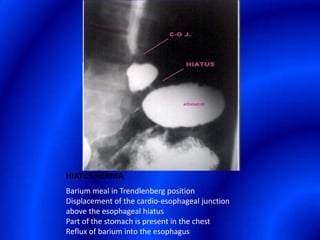

This document provides information about a barium swallow procedure. It begins with an introduction and overview of the embryology and anatomy of the pharynx and esophagus. It then describes the procedure itself, including preparation, technique, views obtained, and indications. Specific conditions that may be examined include pharyngeal and esophageal webs, foreign body impaction, scleroderma, dysphagia, mediastinal masses, and carcinoma. Diagrams are provided to illustrate normal anatomy and various pathological findings.